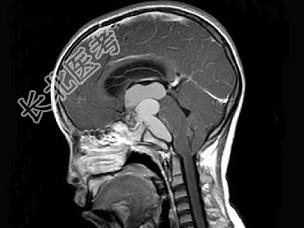

- 单项选择题男,15岁, 2个月前无明显诱因出现头痛,间断性钝痛, 根据所提供图像,最可能的诊断是 ( )

A、垂体瘤

B、颅咽管瘤(造釉细胞型)

C、生殖细胞瘤

D、胶质细胞瘤

E、结核性肉芽肿